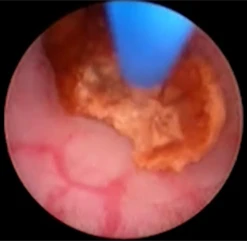

Через рабочий канал уретеропиелоскопа проводится лазерное волокно. По оптическому каналу изображение от эндоскопа передается на монитор. Волокно вплотную подводится к камню и при нажатии на педаль подаётся лазерное излучение, вследствие которого происходит деструкция камня.

Добившись нужной дисперсности фрагментов камня, их элиминируют корзинкой, либо другими видами экстракторов (петли, щипцы). Производится эндоскопическая ревизия мочеточника. Подтверждается полное удаление фрагментов камня. Уретеропиелоскоп удаляется.